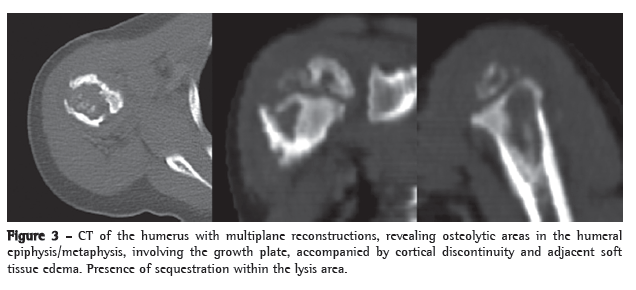

Complementary examinations revealed the following: leukocytes, 8,200 (9% rods and 66% neutrophils); erythrocyte sedimentation rate, 32 mm/h; C-reactive protein, < 6.0 mg/L; normal urine sediment; normal chest X-ray; and strongly positive PPD result, 18 mm. A CT scan of the humerus revealed multiple lytic lesions in the proximal region of the humerus, involving the epiphysis, the metaphysis and the proximal diaphysis, as well as cortical discontinuity and adjacent soft tissue edema (Figure 3).

Lytic and sclerotic bone lesions with periosteal reaction characterize the radiographic lesions. In the case described here, the CT findings in the epiphysis, the metaphysis and the diaphysis were consistent with previous descriptions in young patients. Older children usually present only metaphyseal changes.(4)